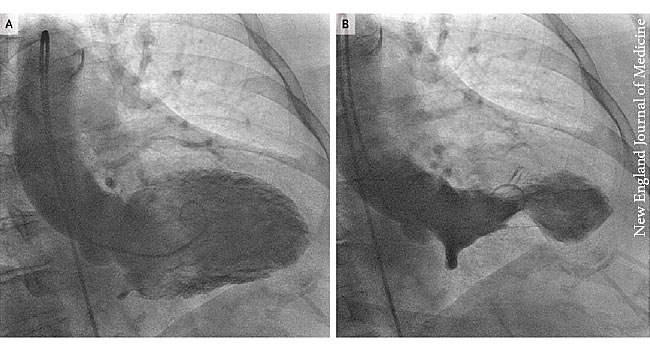

#Grief is more than just sadness -- it can also take a physical toll on your body, including a condition sometimes known as "broken heart syndrome." https://wb.md/36AQqKt pic.twitter.com/WqnM6fT62t